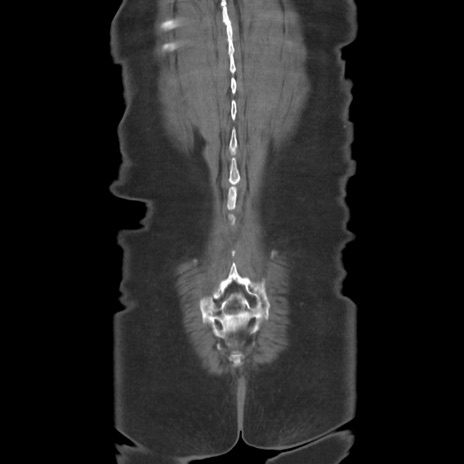

横断像

【症例】80歳代女性

【主訴】下腹部痛

【現病歴】約8時間前より下腹部痛の出現あり、救急外来受診。

【既往歴】両側付属器切除

【身体所見】意識清明、下腹部正中に手術痕あり、その部位に一致して圧痛と反跳痛あり。腸蠕動音は亢進。

【データ】WBC 9300、CRP 0.15